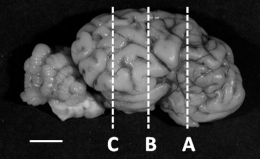

| Cerebrum | |||

| Level A | Median (IQR) | Median (IQR) | |

| Area of cerebrum (mm2) | 266.9 (253.6–311.4) | 280.3 (252.9–304.9) | 0.989 |

| Area of myelin (mm2) | 28.2 (25.8–30.2) | 26.6 (21.2–30.1) | 0.365 |

| Myelin (%) | 10.5 (8.7–11.6) | 9.8 (7.8–11.0) | 0.331 |

| Myelin-periventricular (O.D.) | 0.129 (0.108–0.136) | 0.137 (0.120–0.148) | 0.408 |

| Myelin-intragyral (O.D.) | 0.094 (0.082–0.127) | 0.094 (0.087–0.107) | 0.755 |

| Level B | |||

| Area of cerebrum (mm2) | 402.8 (377.7–413.5) | 404.3 (360.9–441.8) | 0.888 |

| Area of myelin (mm2) | 80.4 (79.6–97.3) | 114.3 (93.7–155.3) * | 0.033 |

| Myelin (%) | 21.4 (19.8–23.5) | 28.5 (25.9–34.3) * | 0.003 |

| Myelin-periventricular (O.D.) | 0.166 (0.144–0.184) | 0.187 (0.171–0.194) | 0.135 |

| Myelin-intragyral (O.D.) | 0.106 (0.090–0.152) | 0.116 (0.111–0.119) | 0.904 |

| Level C | |||

| Area of cerebrum (mm2) | 275.4 (226.3–323.9) | 210.9 (209.7–282.3) | 0.383 |

| Area of myelin (mm2) | 28.9 (19.7–41.0) | 29.9 (28.0–43.8) | 0.889 |

| Myelin (%) | 9.9 (8.0–18.1) | 14.2 (13.3–15.5) | 0.488 |

| Myelin-periventricular (O.D.) | 0.154 (0.112–0.186) | 0.156 (0.147–0.165) | 0.661 |

| Myelin-intragyral (O.D.) | 0.128 (0.067–0.151) | 0.123 (0.107–0.144) | 0.528 |